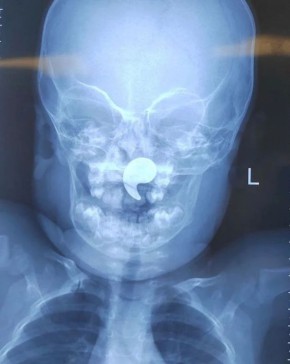

Операцию провели специалисты областной больницы №1 вместе с врачами Бобровской РБ. Внедрение эндокардиального стимулятора было необходимо для коррекции патологии у 86-летней пациентки, страдающей полной поперечной блокадой сердца и приступами потери...